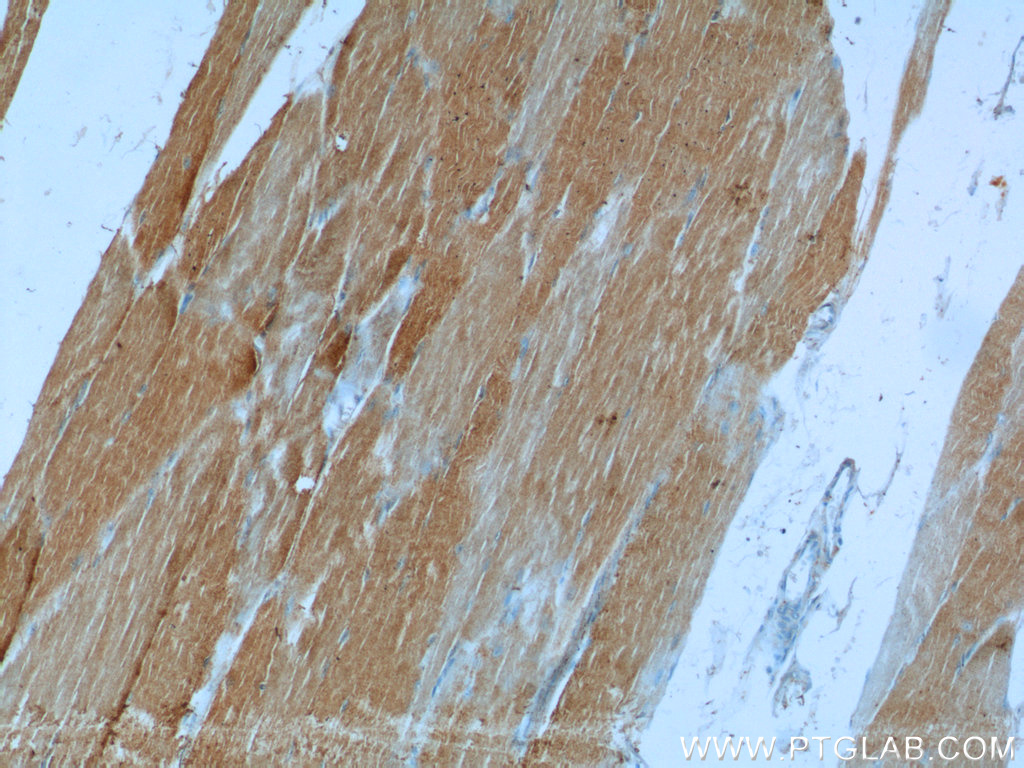

| Positive IHC detected in | mouse liver tissue, human skeletal muscle tissue, human liver tissue, mouse skeletal muscle tissue Note: suggested antigen retrieval with TE buffer pH 9.0; (*) Alternatively, antigen retrieval may be performed with citrate buffer pH 6.0 |